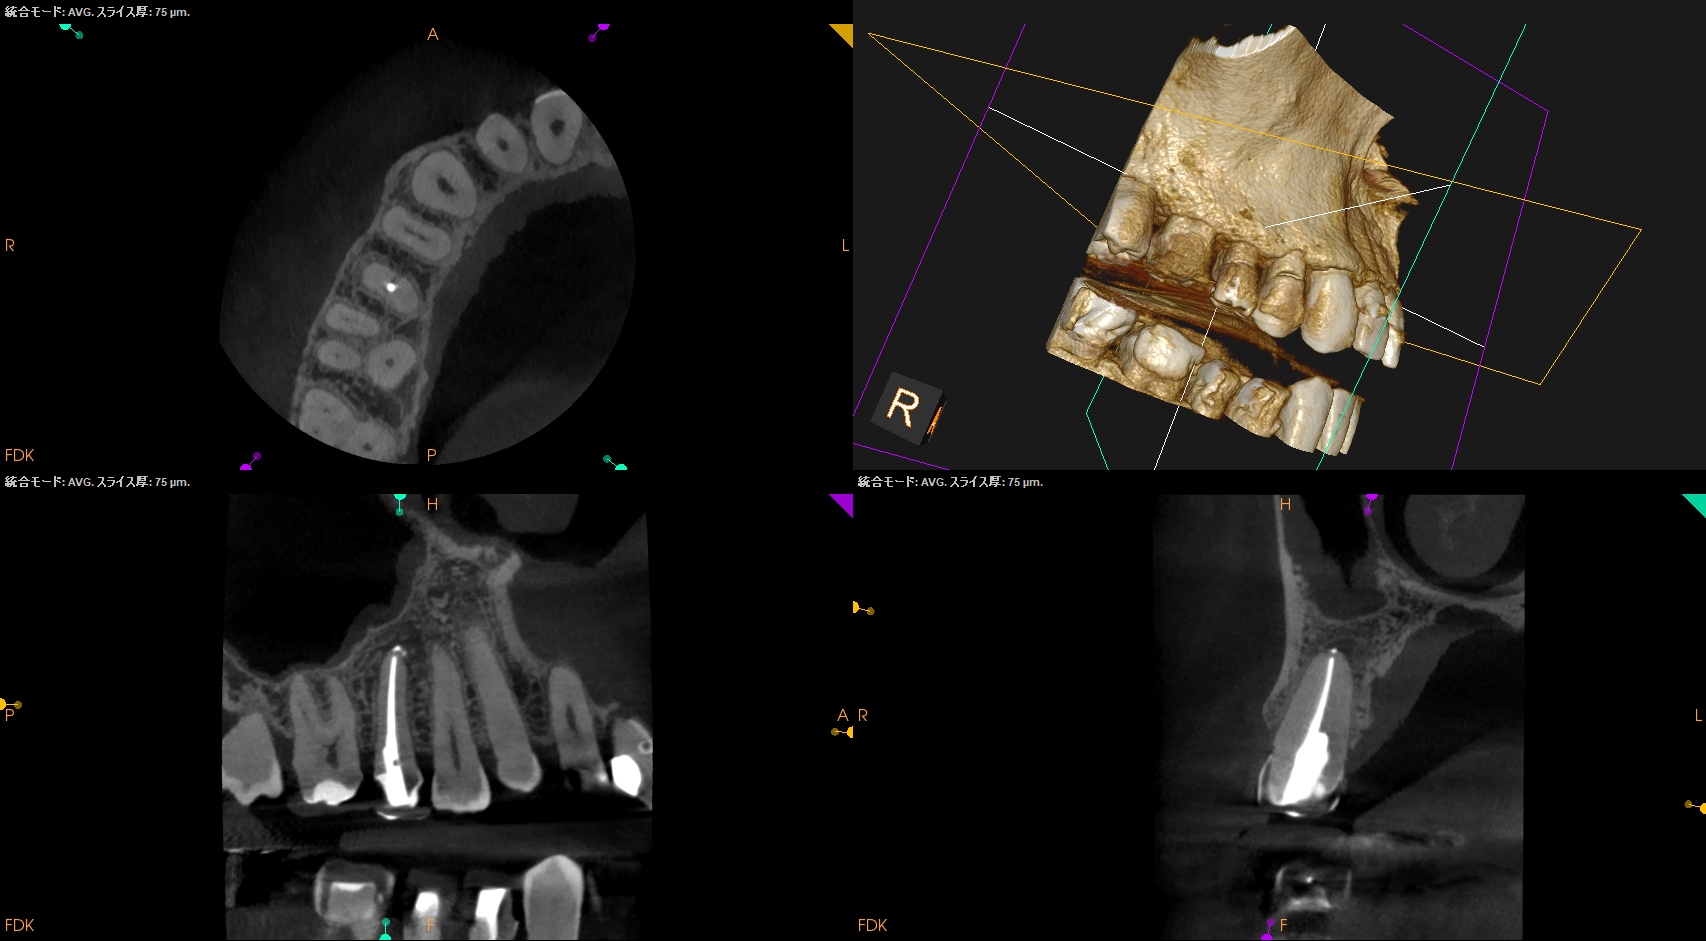

#4 RCT 8M recall(2026.1.26)

初診時と比較した。

根尖病変はほぼ消失した。

最終補綴もOKである。